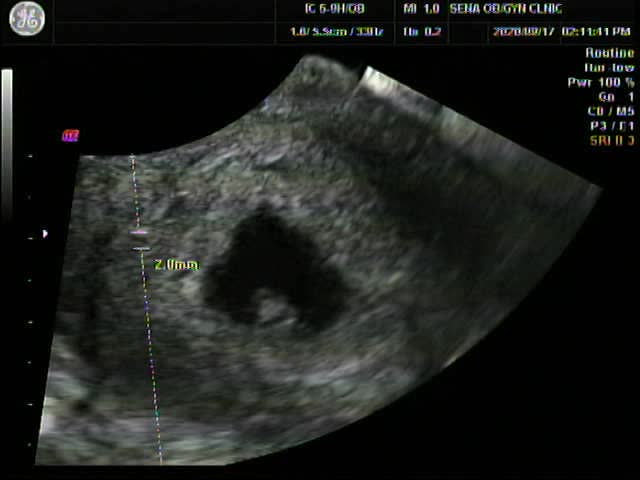

심장소리를 듣다(6주3일)

찰떡이의 존재를 확인 후 약 3주쯤 지났으려나..5주차에 아기집과 난황을 확인! 1주일뒤 9월17일 6주3일이 ...